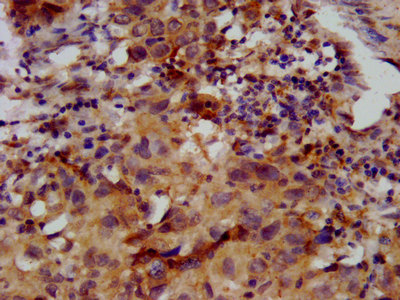

IHC image of CSB-PA862050LA01HU diluted at 1:400 and staining in paraffin-embedded human ovarian cancer performed on a Leica BondTM system. After dewaxing and hydration, antigen retrieval was mediated by high pressure in a citrate buffer (pH 6.0). Section was blocked with 10% normal goat serum 30min at RT. Then primary antibody (1% BSA) was incubated at 4°C overnight. The primary is detected by a biotinylated secondary antibody and visualized using an HRP conjugated SP system.

IHC image of CSB-PA862050LA01HU diluted at 1:400 and staining in paraffin-embedded human placenta tissue performed on a Leica BondTM system. After dewaxing and hydration, antigen retrieval was mediated by high pressure in a citrate buffer (pH 6.0). Section was blocked with 10% normal goat serum 30min at RT. Then primary antibody (1% BSA) was incubated at 4°C overnight. The primary is detected by a biotinylated secondary antibody and visualized using an HRP conjugated SP system.